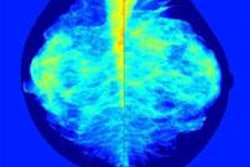

When it comes to screening women for breast cancer, those with dense breasts or tissue abnormalities tend to be the most troublesome, but breast ultrasound has proved, and continues to prove, its utility for these women, say leading researchers.

Estimates for mammography sensitivity range anywhere from 65% to 91%, and the masking effect of dense breast tissue is the most relevant cause of false negatives, according to Dr. Veronica Girardi from the Istituti Ospedalieri Bresciani in Brescia, Italy, a speaker at today's ECR 2015 refresher course.

"When we consider breast density, there are two different issues: One is that it's influencing cancer detection on mammographic imaging, and the second is its possible independent effect on breast cancer risk," she noted. "Breast density is significantly associated with an increased risk of breast cancer at any age, but it does not seem to influence ultrasound accuracy. For this reason, the association of ultrasound to mammography in women with dense breasts has been proposed by many authors, although there is no evidence of mortality reduction."

Girardi advocates ultrasound because, especially compared with mammography and MRI, it is quick, widely available, well-tolerated, very safe, and relatively cheap. In addition, it can boost cancer detection by about 2.9%, as found in a recent study by her group. However, ultrasound may increase false-positive biopsies.